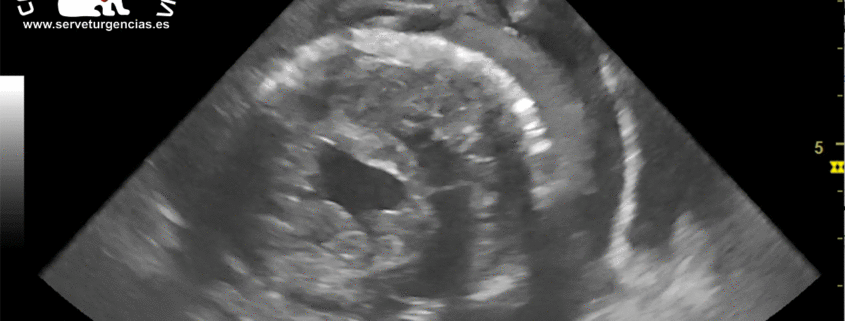

Tromboembolismo aurícula izquierda

El tromboembolismo aórtico (ATE) es un proceso por el cual se forma un trombo, típicamente en la aurícula izquierda